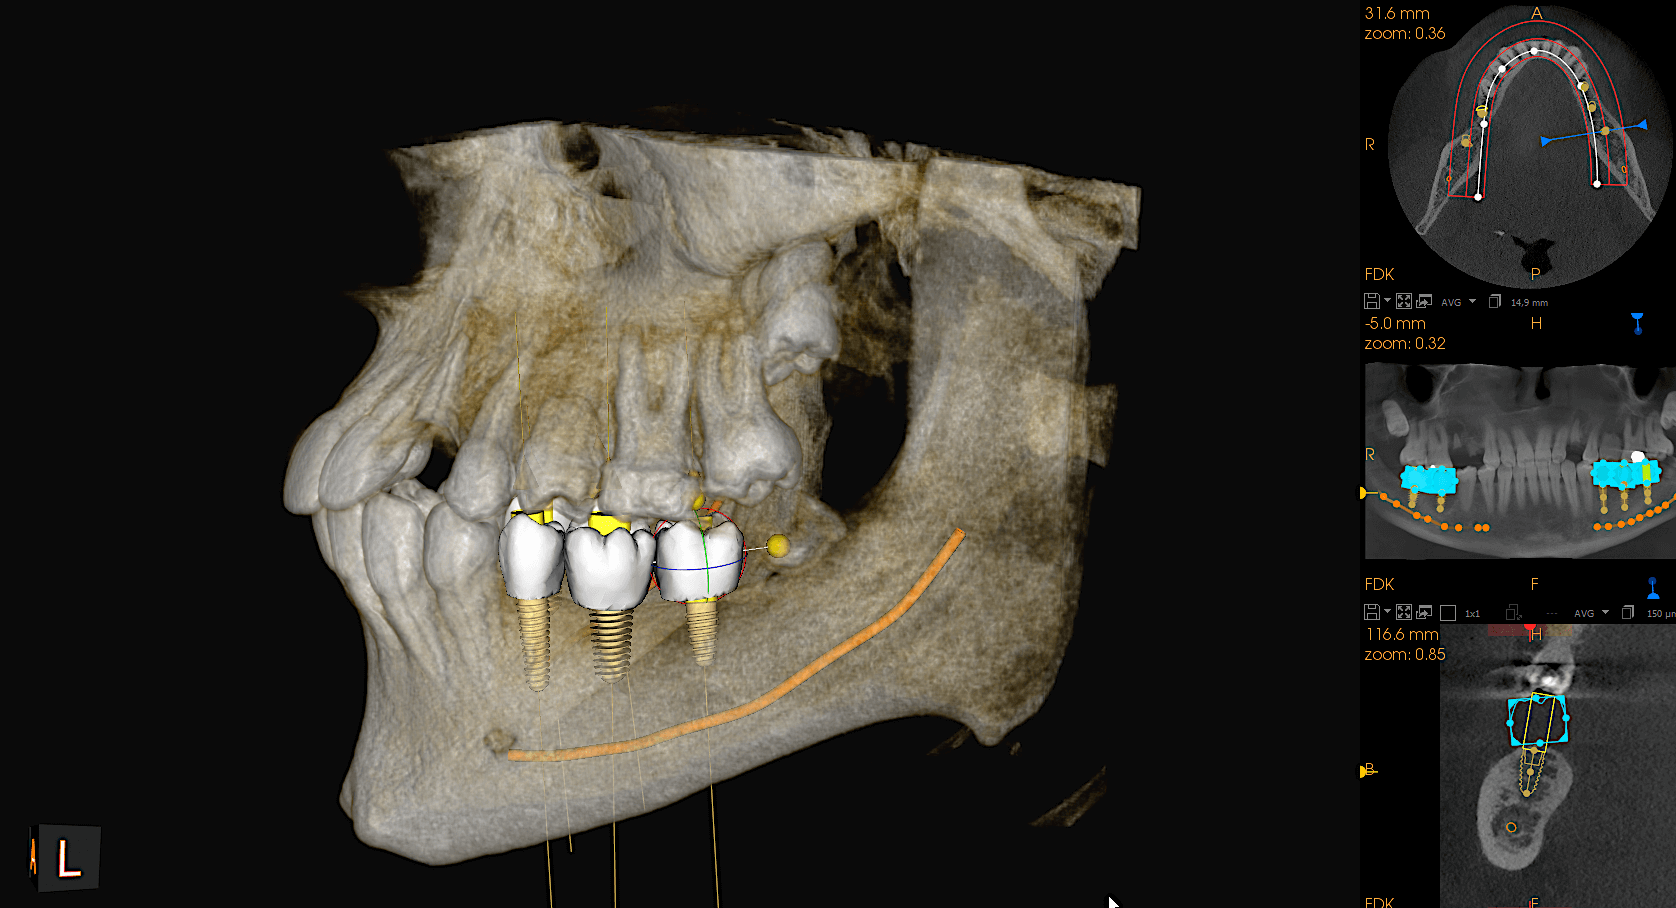

Planowanie implantów

tomografia szczęki w Białymstoku

tomografia szczęki Białystok